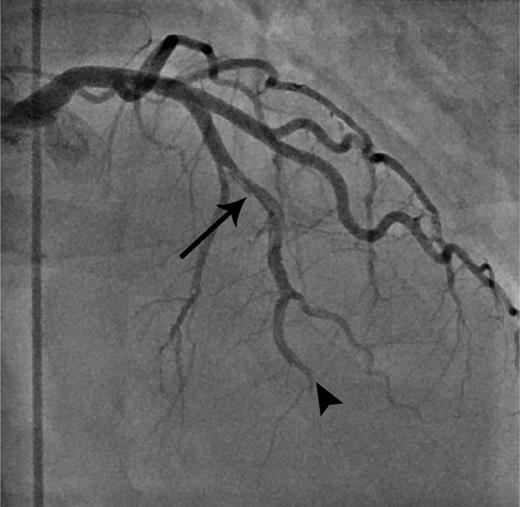

The patient started complaining of intermittent chest pain and shoulder pain during the bone marrow infusion. Peak systolic and diastolic blood pressures were 168 and 106 mm Hg, heart rate of 220 beats per minute. An electrocardiogram remained unchanged and nondiagnostic in the presence of a known left bundle branch block. Troponin T serum concentration was elevated at 1.8 ng/mL (normal <0.01). A stat echocardiogram demonstrated akinesis of the apex and midventricular wall, and an EF of 27% suggestive of an acute coronary syndrome. A coronary angiogram demonstrated a dissection of the mid left anterior descending artery with thrombus formation and thrombotic occlusion of the distal left anterior descending artery (Figure 1). No coronary intervention was pursued but an intra-aortic balloon was placed for coronary perfusion support. She eventually had an uneventful recovery and continues to do well 3 months after her transplant with improvement in her EF (50% with improvement in wall motion abnormalities).

Coronary angiogram. Right anterior oblique cranial projection outlining the typical angiographic appearance of coronary artery dissection of the mid segment of the left anterior descending artery (arrow). Furthermore, it reveals an abrupt cutoff of the distal left anterior descending artery consistent with thrombotic occlusion (arrowhead).